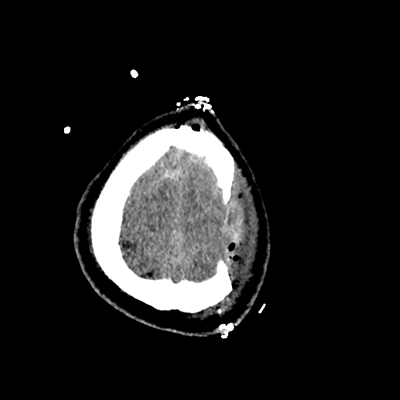

On day 5 of admission, he begins having intracranial hypertension again, spiking up to 40mmHg. You bolus with propofol and fentanyl, to no avail. You then push 30mL of 23.4% NaCl, which provides some brief improvement, allowing you to quickly get a non-contrast head CT. Unfortunately, he's now back up to 36mmHg. You review his labs, and note the following: Na 150, K 3.8, Cl 119, HCO3 18, BUN 21, Cr 0.85, glucose 136, sOsm 320.

NCHCT

NCHCT 7/20 7/20

NCHCT 8/20 8/20